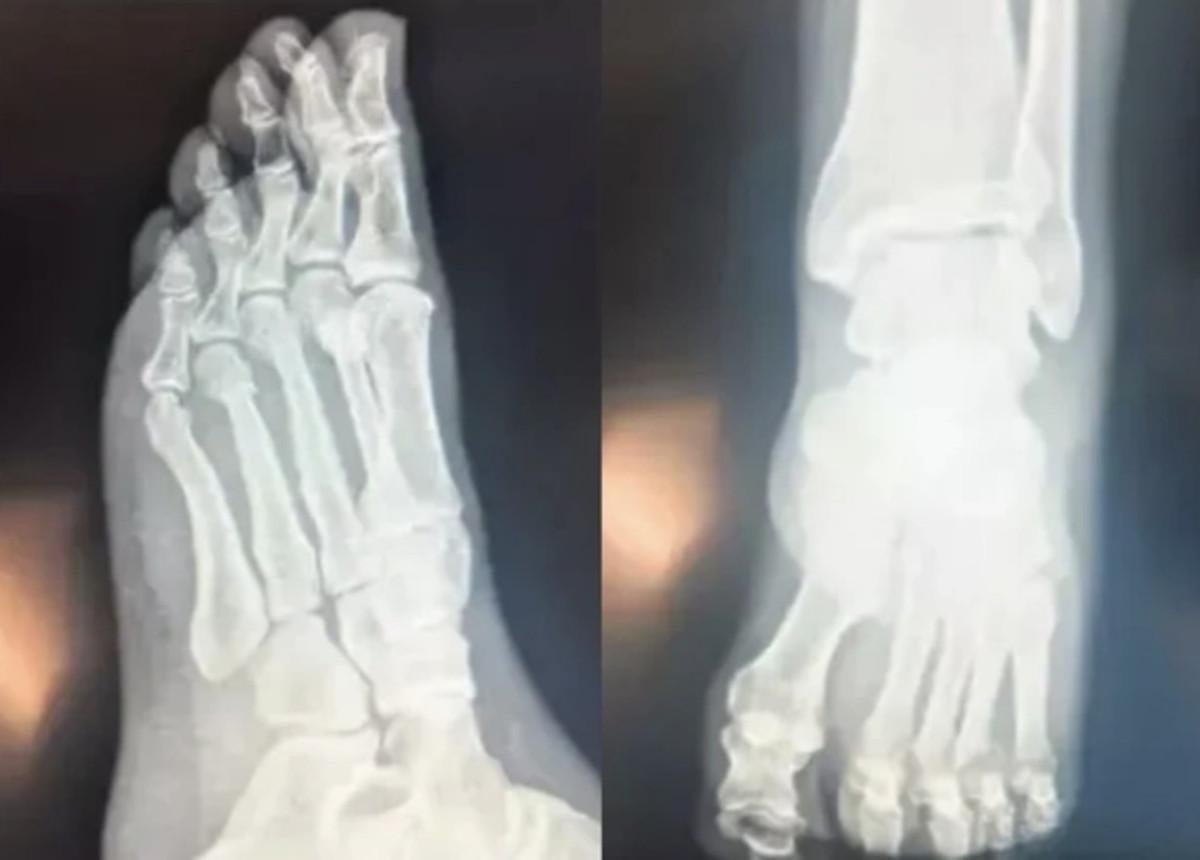

BU KEZ RÖNTGEN FİLMLERİNİ PAYLAŞTI

Saygı Öztürk'e konuşan Özel, ayrıca ayak röntgen filmlerini paylaştı.